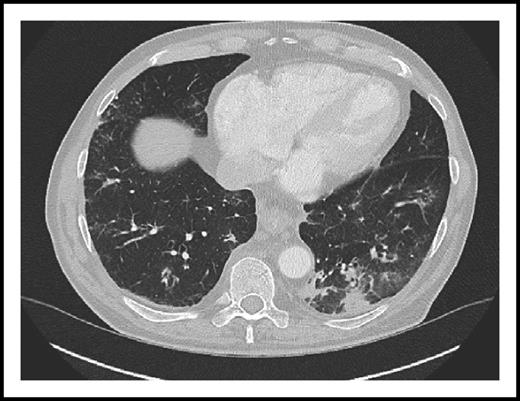

CT scan of the chest from a patient on ibrutinib monotherapy showing interstitial (ground glass) pulmonary infiltrates caused by Pneumocystis pneumonia. See the complete Figure 1 in the article by Ahn et al that begins on page 1940.

Most CLL patients with PCP have previously presented with severe respiratory symptoms (cough and dyspnea), hypoxia, interstitial (ground glass) pulmonary infiltrates on computed tomography (CT) scans (see figure), and fewer P. jirovecii organisms in bronchoalveolar lavage (BAL) fluid than patients with AIDS.2,3 Initiation of anti-Pneumocystis therapy often exacerbated respiratory compromise, a complication that could respond to treatment with corticosteroid therapy. PCP in patients with hematological malignancies including CLL has previously been associated with a high risk of mortality.2 In contrast, the CLL patients with PCP reported by Ahn et al had higher CD4+ T-cell counts, less severe and more treatment responsive PCP, and no mortality.